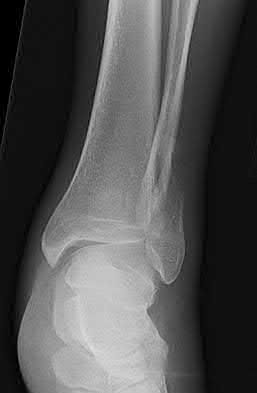

A 28-year-old male sustains a severe hyper-dorsiflexion injury to his ankle in a motor vehicle accident, resulting in a Hawkins Type III talar neck fracture. Which of the following arteries provides the predominant blood supply to the body of the talus, placing it at significant risk for avascular necrosis in this injury?

The artery of the tarsal canal, which is a branch of the posterior tibial artery, provides the dominant blood supply to the talar body. In a Hawkins Type III fracture (talar neck fracture with subtalar and tibiotalar dislocation), the blood supply from the artery of the tarsal canal, the artery of the sinus tarsi, and capsular vessels are disrupted, leading to an avascular necrosis (AVN) rate approaching 100%.